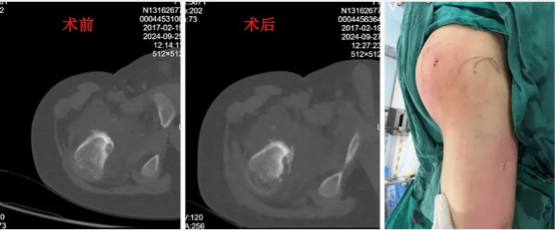

男性,17岁,因“左小腿疼痛10月余”就诊,患者10月前无明显诱因开始出现间歇性疼痛不适,夜间疼痛明显,口服塞来昔布可以缓解,逐渐加重。于当地医院就诊,行胫骨X线、CT及MRI检查,诊断为骨样骨瘤,当地医生无法确定,遂介绍至我院就诊。术前考虑患者为皮质型骨样骨瘤,瘤巢刺激骨皮质,胫骨内侧骨皮质增厚伴瘤巢形成,疼痛较为明显,但局部骨质太硬,单纯射频消融可能无法奏效,热量无法传导,导致消融范围失效,遂考虑采用导航下行左侧胫骨病灶超声骨刀磨除术的策略,采用水木天蓬超声骨刀铣刀头搭载Suretack连接S8导航系统。术后第二天患者自诉原有夜间疼痛有缓解,术后一个月基本感觉不到原来的疼痛。术后复查CT可见骨内明显的磨除隧道。

图6:术前左侧胫骨中下段影像检查提示骨皮质增厚

图8:术中导航及超声骨刀磨除

图9:术后复查CT见超声骨刀磨除的隧道